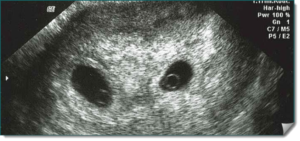

При двойне врач считает количество плодных яиц. Если каждый зародыш находится в своем округлом темном пятне, то врач делает вывод о наличии в утробе двойняшек. Если на снимке видно, что два эмбриона находятся в общем яйце, то ожидается рождение однояйцевых близнецов.

Фото УЗИ двойни на ранних сроках беременности, 8 недель

В 8 акушерских недель (или 6 недель от момента зачатия) обычно используют трансвагинальный способ УЗИ. Аппарат вводят внутрь, чтобы лучше разглядеть эмбрионы. На мониторе видны два или три темных пятна. Врач измеряет длину зародышей и фиксирует несколько сердцебиений.